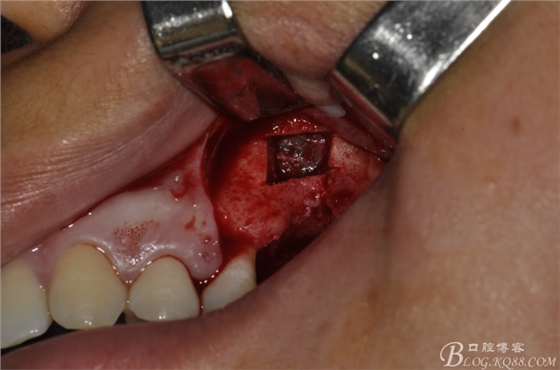

術(shù)中照片。

超聲骨刀切開(kāi)骨外板